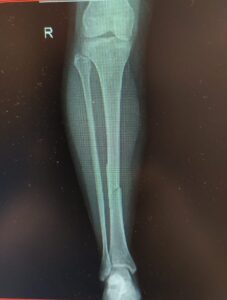

if the fracture is displaced, surgery may be needed to put the bone back into the correct position and fix the bone with Plates & screws or nails for adequate healing to occur.

- Tibia Fractures.